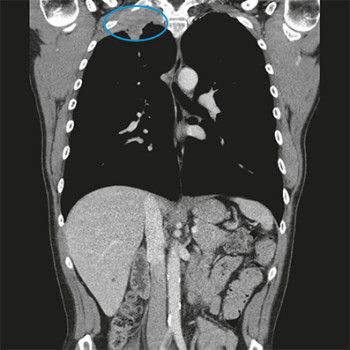

De pancoasttumor: witte raaf bij schouderpijn

Een 50-jarige man bezoekt het spreekuur met pijn rondom zijn rechterschouder. De pijn is er sinds een week en zit ter hoogte van zijn rechterbovenarm, oksel, schouderblad en aan de bovenzijde van zijn schouder. De patiënt voelt ook een licht drukkend gevoel op de rechter…